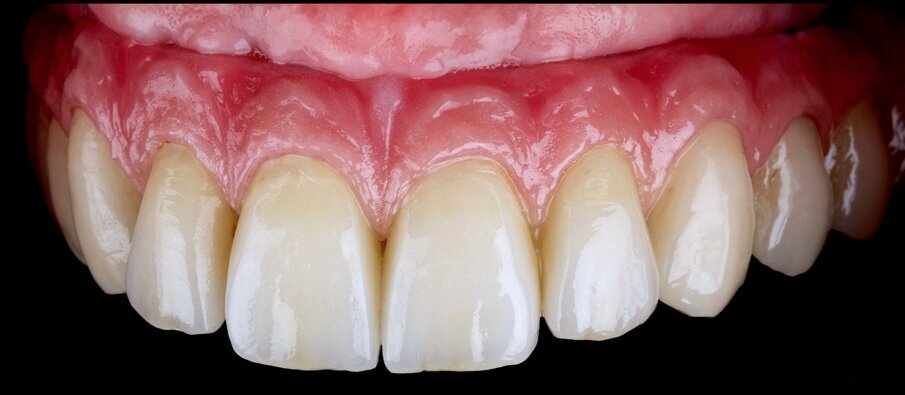

The finished restoration placed in the mouth showed good integration (Figs. 19 & 20). The correct implant seating was verified with a CT scan (Fig. 21). The basal adaptation was perfect to enable optimal cleaning of the mucosa. Occlusal fit was checked with active posterior cusps and canine and protrusive guidance.

Fig. 19: Intra-oral view after treatment.

Fig. 20: Frontal view after treatment.